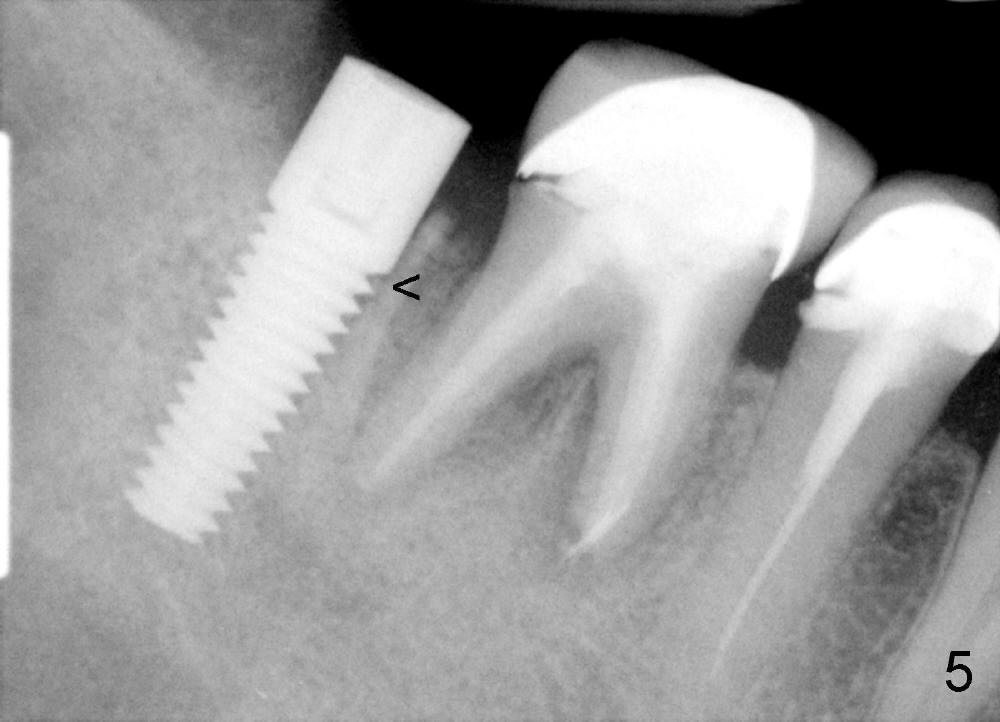

Three and a half months postop, the density of the previous cyst area increases apparently, while the bone grows into the threads of the implant (Fig.5 <, as compared to the same area of Fig.3,4).  The implant is ready for restoraton.